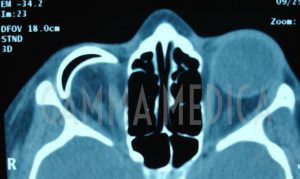

Negli ultimi anni ci sono stati notevoli sviluppi e perfezionamenti nella chirurgia della cavità anoftalmica sia nella fase di pianificazione di asportazione del contenuto dell’orbita sia nella fase di ricostruttiva. Come per altre procedure di microchirurgia oftalmica, l’asportazione di un occhio malato e non vedente, deve essere effettuata meticolosamente per ottenere il miglior risultato funzionale ed estetico e per evitare sequele che possano aggravare ulteriormente la già difficile condizione dei pazienti. La rimozione dell’occhio o del contenuto dell’orbita, è una delle decisioni più gravi e difficili di un paziente e del medico che deve eseguire questo intervento.

Esistono vari tipi di intervento in relazione allo stato del bulbo oculare o alla causa che ne ha determinato la malattia e la cecità.

- Enucleazione: rimozione del globo, compresa la cornea, sclera, e una porzione del nervo ottico.

- Eviscerazione: rimozione del contenuto del globo lasciando il nervo ottico e sclera in situ.

Sia nel caso di enucleazione, sia in quello di eviscerazione viene ricostituito il contenuto dell’orbita inserendo un impianto endoorbitario con biglie di idrossiapatite (materiale biocompatibile di sintesi molto poroso, facilmente colonizzabile e vascolarizzabile allo strato superficiale) o PMMA (polimetilmetacrilato). L’impianto primario, inserito nella sclera, va suturato ai quattro muscoli retti per trasmettere il movimento Pur essendo fondamentale per il risultato funzionale e cosmetico l’impianto può presentare dei problemi postoperatori quali esposizione o estrusione.